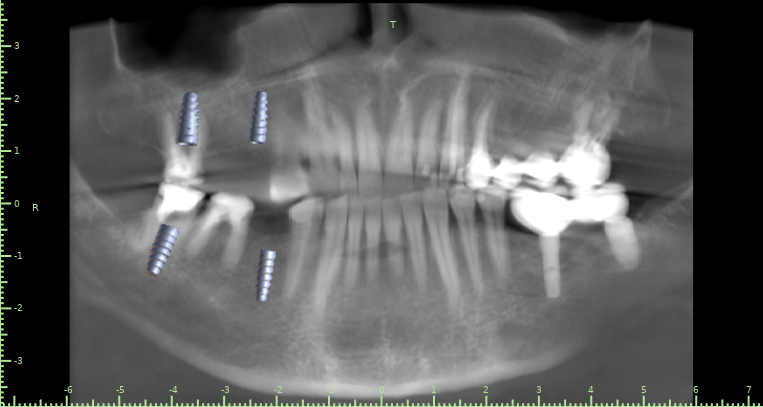

Женька Опубликовано 10 декабря, 2021 Поделиться Опубликовано 10 декабря, 2021 Клинически показалось очень мало места для адекватной коронки. Не помешает ли вестибулярная кортика интрузии? Ссылка на комментарий

Женька Опубликовано 10 декабря, 2021 Автор Поделиться Опубликовано 10 декабря, 2021 @kamranchick чисто винтами? или нужно ортодонта подключить? Планируется вот так Ссылка на комментарий

АнтонТЛТ Опубликовано 10 декабря, 2021 Поделиться Опубликовано 10 декабря, 2021 А ортопед не хочет немного шлифануть этот зуб? Винты ставить из-за 1.5 мм, как-то жёстко) Планирование в каком софте? 2 Ссылка на комментарий

Женька Опубликовано 11 декабря, 2021 Автор Поделиться Опубликовано 11 декабря, 2021 @АнтонТЛТ blue sky plan Антон, я передам эти мысли ортопеду А подождите, я же скорее всего сам и буду это протезировать . И пожалуйста, объясните мне когда можно шлифовать, а когда это овер трит. Я же правильно понимаю, что немного шлифануть, это оставить его без покрытия коронкой? Ссылка на комментарий